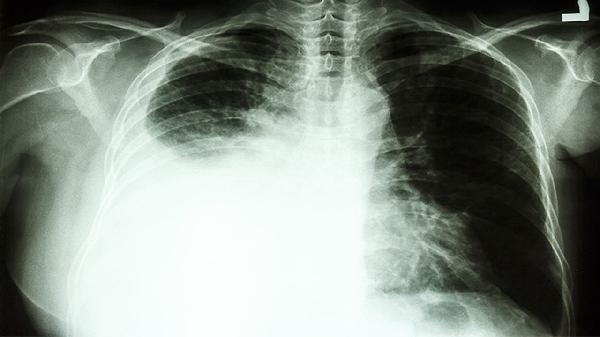

3、良性病变如肝硬化、肺纤维化等同样可能导致癌胚抗原偏高。这些疾病引起的组织损伤会释放癌胚抗原。治疗需针对原发病,如肝硬化患者需戒酒并服用保肝药物,肺纤维化可使用免疫抑制剂。